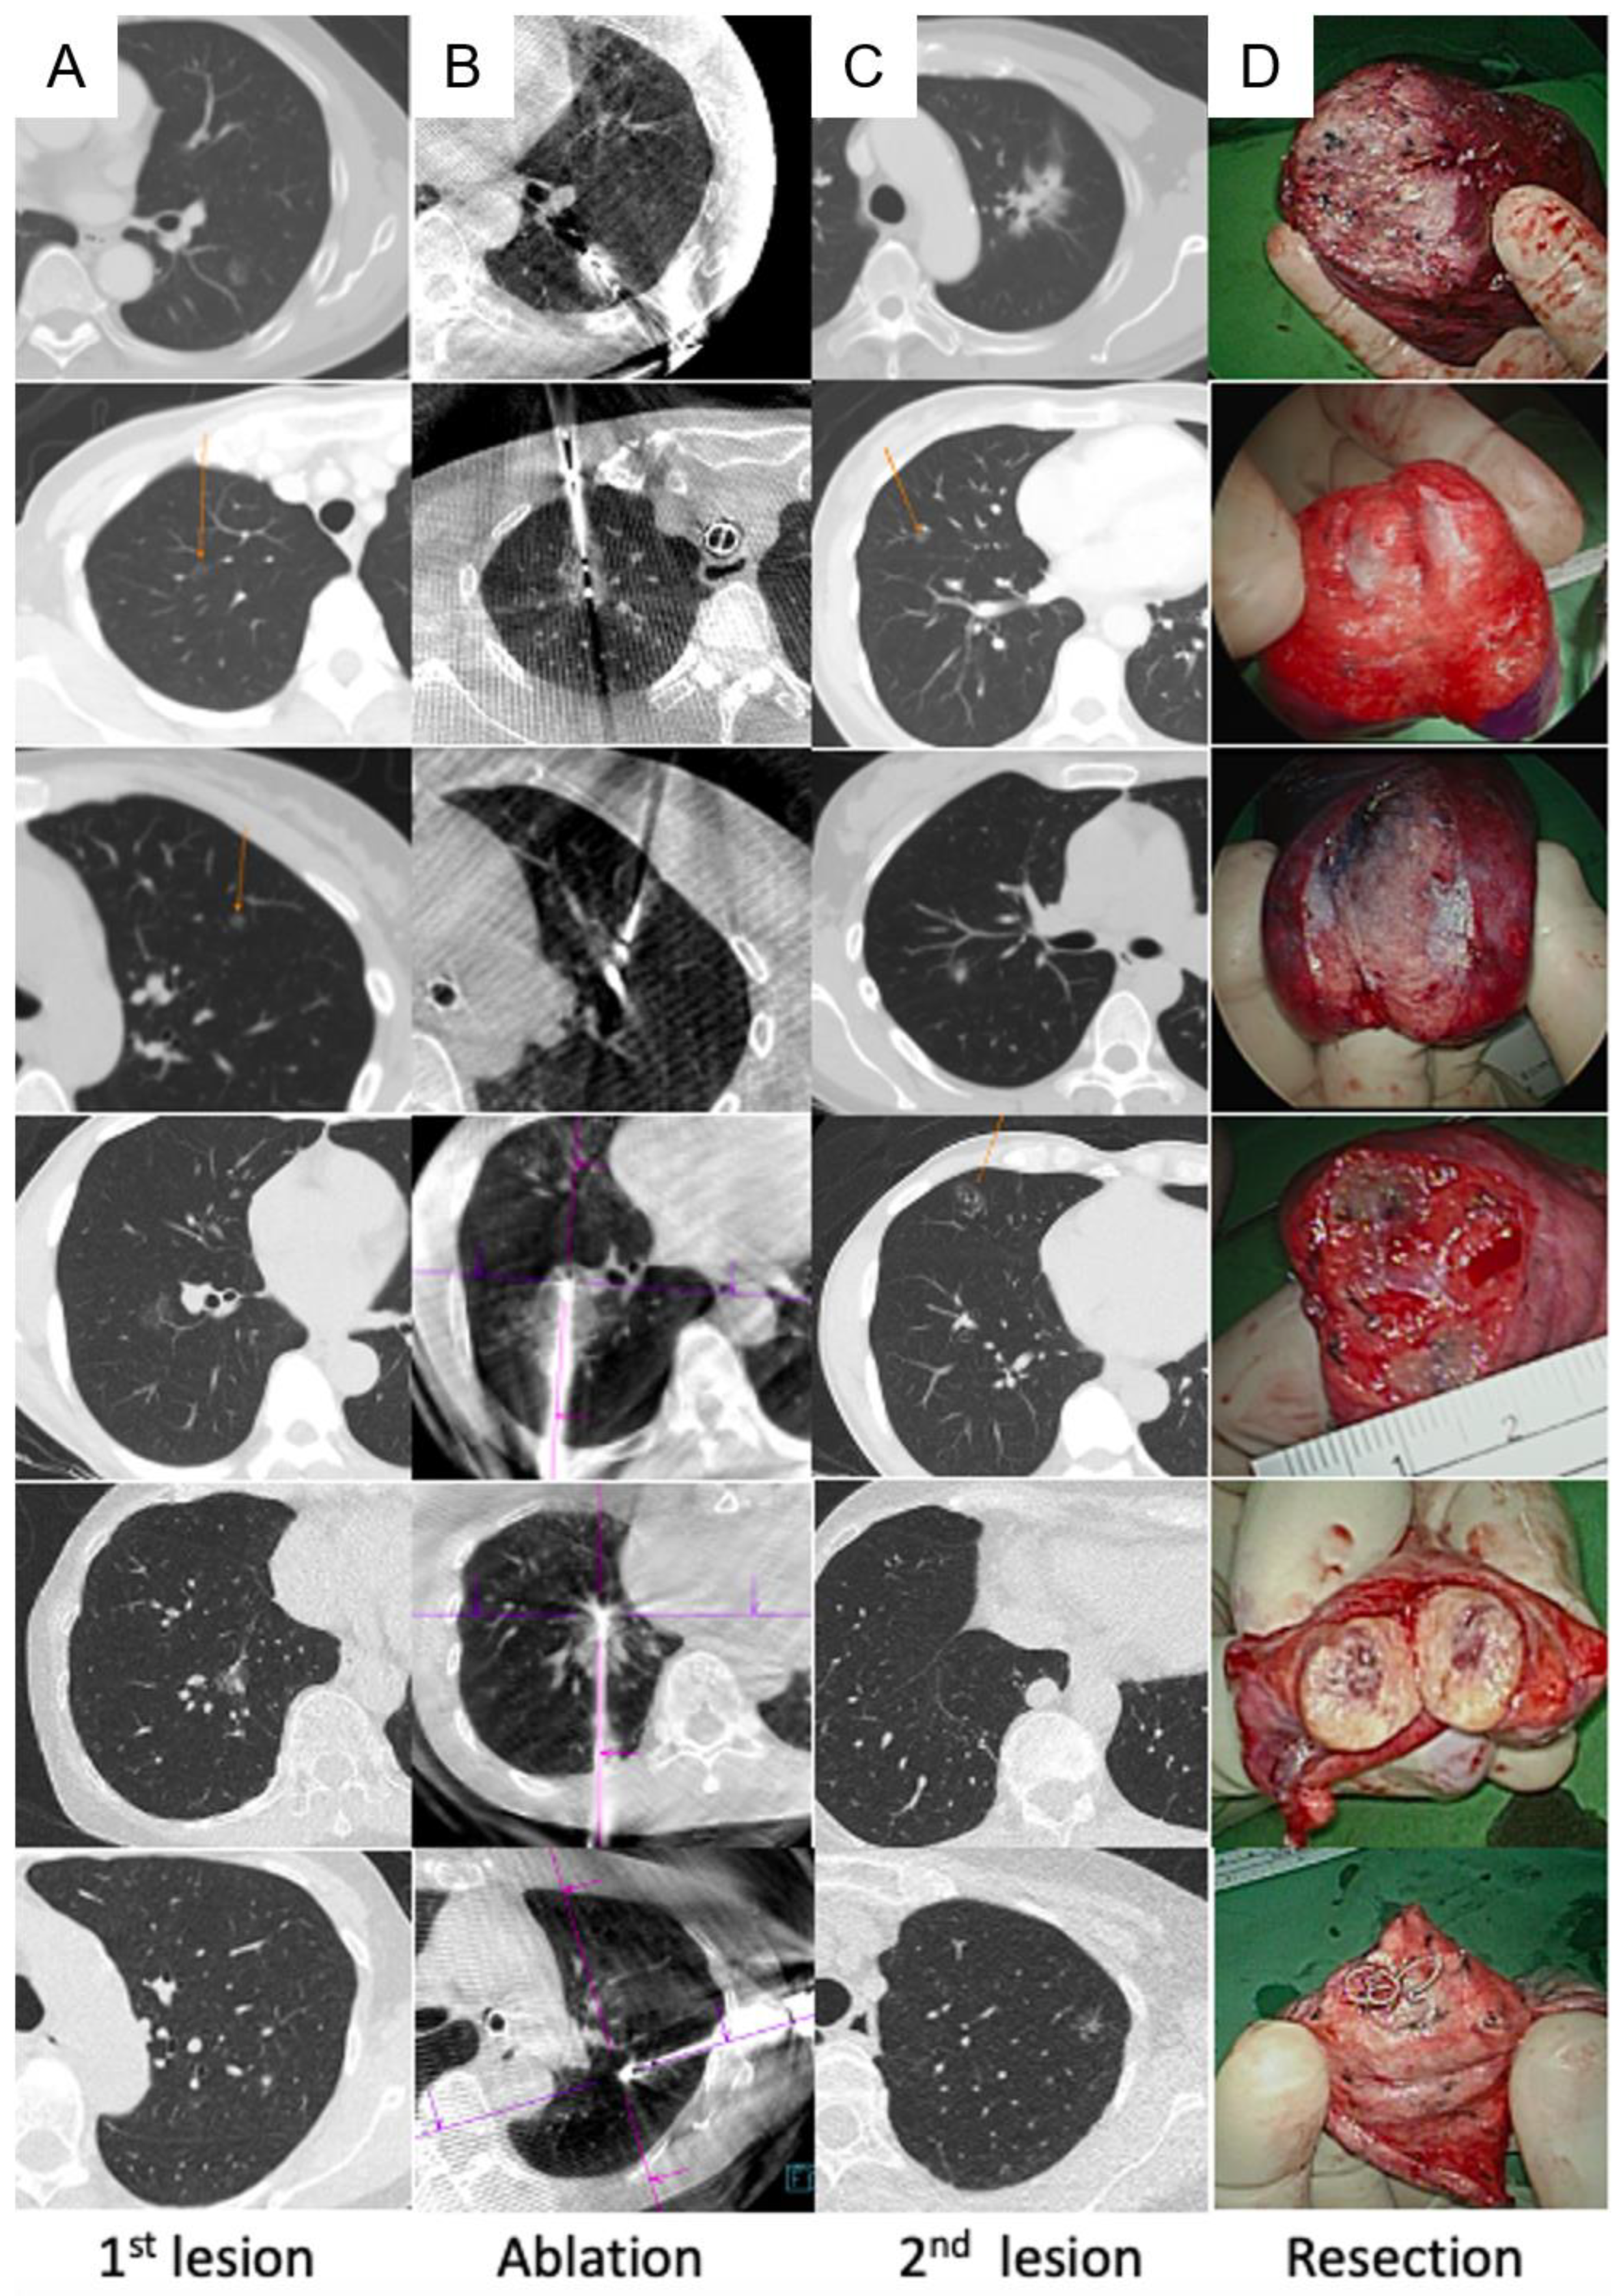

- Harrison, O.J.; Sarvananthan, S.; Tamburrini, A.; Peebles, C.; Alzetani, A. Image-guided combined ablation and resection in thoracic surgery for the treatment of multiple pulmonary metastases: a preliminary case series. JTCVS Tech 2021, 9, 156–162. [Google Scholar] [CrossRef] [PubMed]

- Chang, L.K.; Yang, S.M.; Chung, W.Y.; Chen, L.C.; Chang, H.C.; Ho, M.C.; Chang, YC.; Yu, C.J. Cone-beam computed tomography image-guided percutaneous microwave ablation for lung nodules in a hybrid operating room: an initial experience. Eur Radiol 2024, 34, 3309–3319. [Google Scholar] [CrossRef] [PubMed]